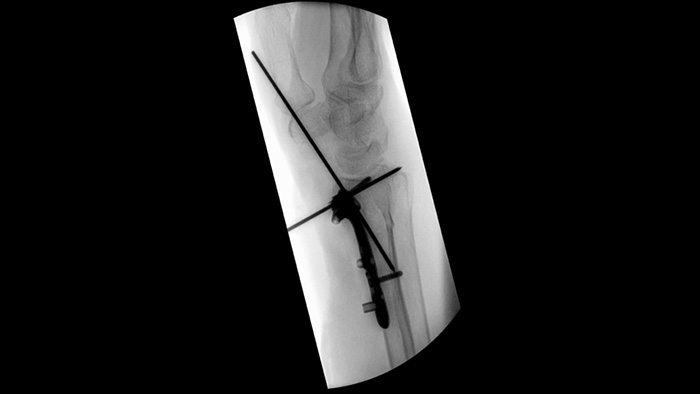

When setting pedicle screws for a spinal fusion or fracture repair, reducing technical distractions and discussions can help surgical teams remain focused on the patient. With Unify workflow’s navigation aids, surgical teams experienced smoother interactions and less miscommunication in a usability study.1

Simplify workflow for challenging orthopedic cases requiring frequent re-positioning of the mobile C-arm. With Position Memory,2 participants in a usability study1 achieved 94% first-time-right repositioning and experienced less frustration during (re)positioning tasks.

Unique asymmetric shutters increase collimation flexibility and help you collimate the anatomy using independent shutter placement with a fingertip. You can adjust shutters and image orientation while on last image hold without using radiation.